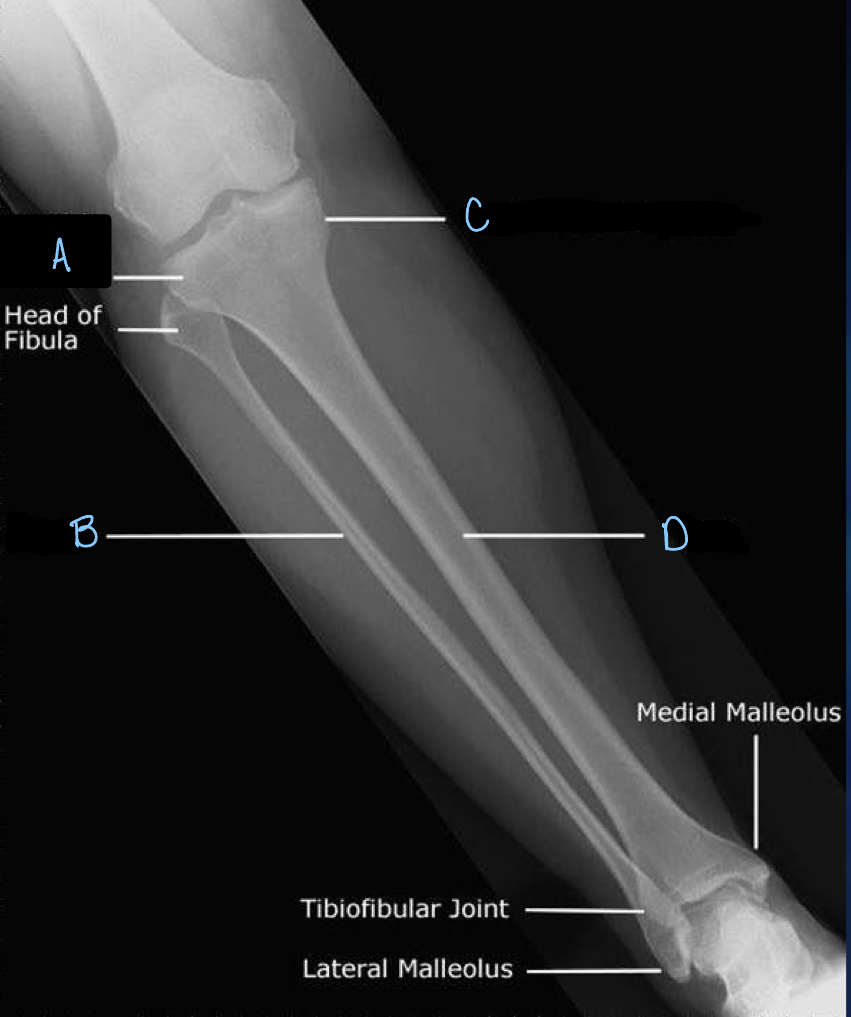

5

What is A?

patella

6

What is B?

tibia

7

What is C?

fibula

8